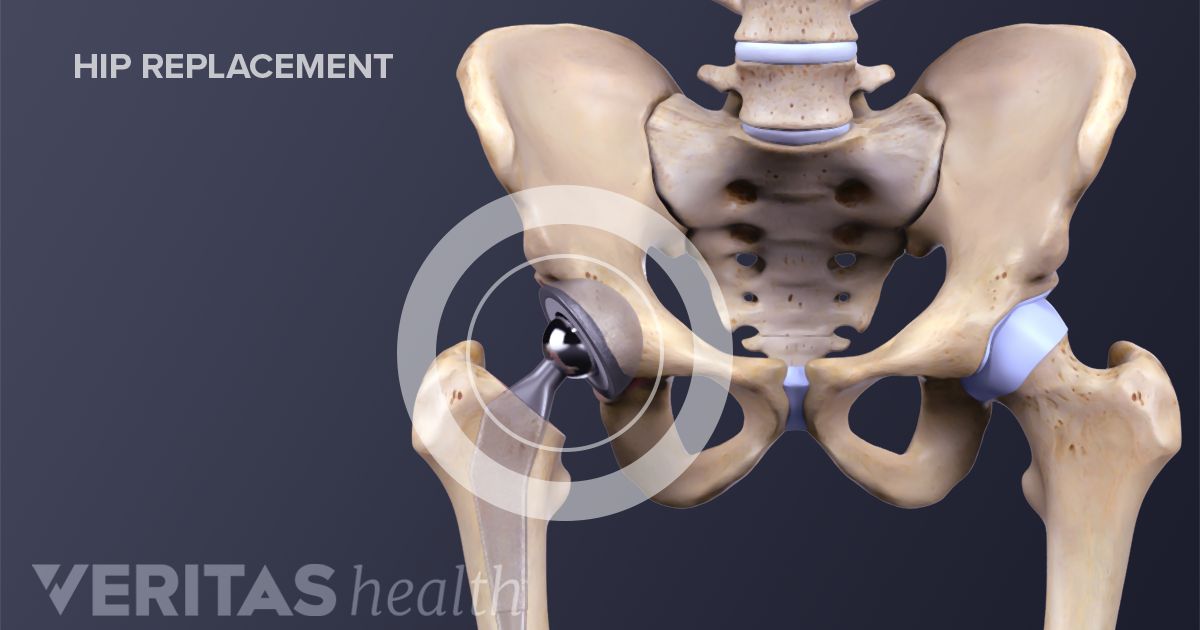

What Is Hip Joint Replacement

What Is Hip Joint Replacement

Total Hip Replacement OrthoSport Victoria

Total Hip Replacement BJISG

Total Hip Replacement Hip Osteoarthritis